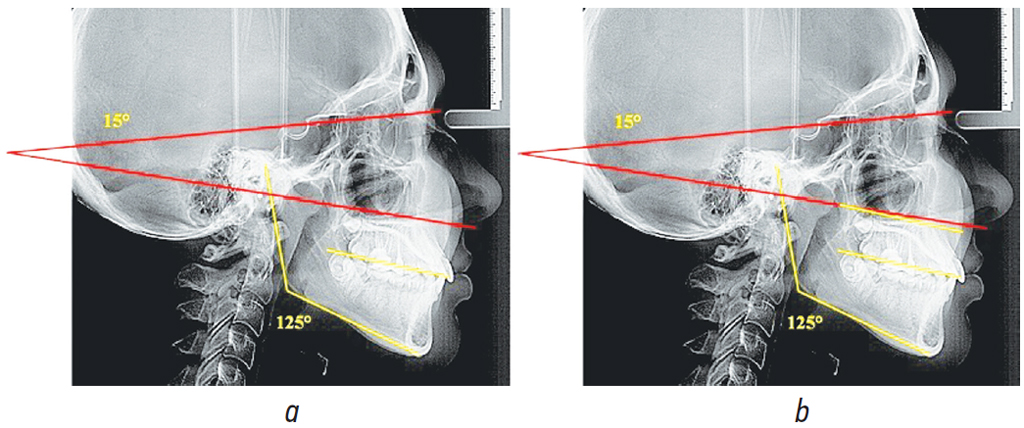

Проанализировано 22 телерентгенограммы, по величине нижнечелюстного угла отнесенные к вертикальному типу роста челюстей (3-я группа). В относительных величинах количественный показатель исследуемой группы составил 32,84 ± 5,73 %.

Величина нижнечелюстного угла в среднем по группе с горизонтальным типом роста составляла 125,94° ± 1,79°, что достоверно отличалось от показателей величины угла в 1-й и 2-й группах исследования (p < 0,05). В 3-й группе величина угла, образованного камперовской горизонталью и плоскостью основания черепа, составляла 15,62° ± 0,73°, по этому показателю нами не отмечено различий (p > 0,05) между 1-й и 2-й группами наблюдений (рис. 4).

Рис. 4. Особенности расположения линий и углов (а) и сопоставительный анализ камперовской и окклюзионной линий (b) в 3-й группе

Fig. 4. Arrangement of lines and angles (a) and comparative analysis of the Camper and occlusal lines (b) in group 3

Характерная особенность сопоставительного анализа расположения камперовской горизонтали с окклюзионной линией — они располагались не параллельно друг другу. В сопоставлении анализируемые линии образовывали острый угол, открывающийся кпереди, в отличие от 1-й и 2-й групп.

Полученные данные свидетельствуют о том, что у людей с вертикальным типом роста, также как и с горизонтальным, не рекомендуется в качестве ориентира использовать камперовскую горизонталь и необходимо выбирать другие ориентиры для конструирования окклюзионной плоскости.